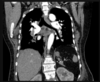

2 anos, masculino

Cisto de duplicação esofágico

Predleção por meninos; diagnosticados na infância

Em geral assintomáticos; podem provocar estridor

Mais comuns no esôfago distal; geralmente não comunicam com a luz do esôfago;

TC: Cisto com densidade de líquido, margens bem definidas que podem realçar com contraste; podem complicar com hemorragia, infecção: nível liquido, espessamento parietal.